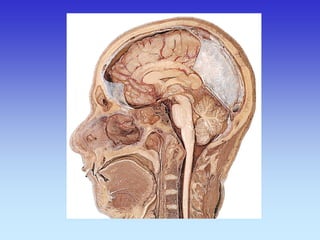

Sagitalni presjek

Koronarni presjek